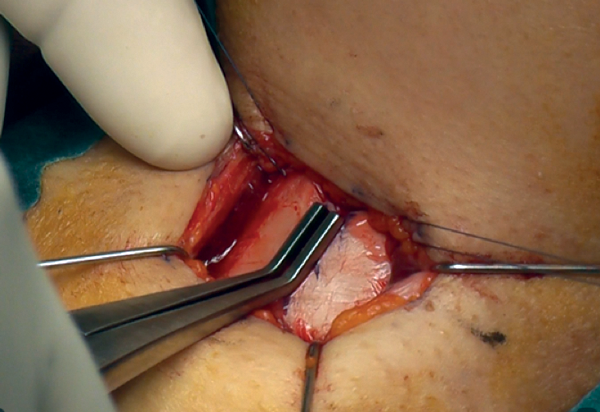

Completion of inner perichondrial elevation

The third stage is performed after drilling and separating the cartilage in the midline.

The inner perichondrium is freed by sharp scissor dissection laterally and towards the centre by just 2mm (Figure 13). This step is performed to allow ease of sliding in the bridge superiorly and inferiorly.

Figure 13: Completion of inner perichondrial elevation.